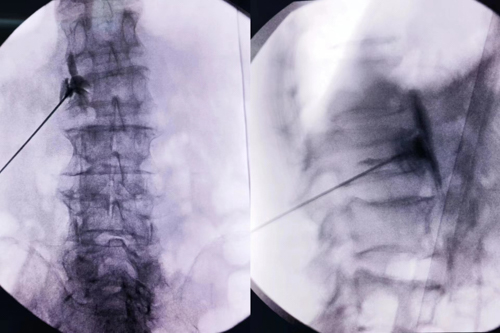

本次来骨科住院时患者左足再次出现足趾坏疽伴感染面临截趾,患者担心术后创面不愈合,瞿创业副主任医师带领其团队仔细研究患者病情,诊断明确,患者病程长,且长期处于下肢疼痛状态,左下肢缺血情况严重,综合考虑后,建议先行C型臂引导下经皮穿刺腰交感神经节阻滞+射频脉冲调控术,改善下肢血液供应,再行截趾手术。

2024年3月9日,瞿创业副主任医师团队顺利完成医院首例C型臂引导下经皮穿刺腰交感神经节阻滞+射频脉冲调控术,填补医院在该领域内的空白。术后患者左侧肢体明细皮温增高,血运明显改善,为患者进行截肢手术创造良好条件,也很好预防了患者肢体进一步发生坏死,该技术为糖尿病足等下肢血管闭塞性疾病患者带来了福音。